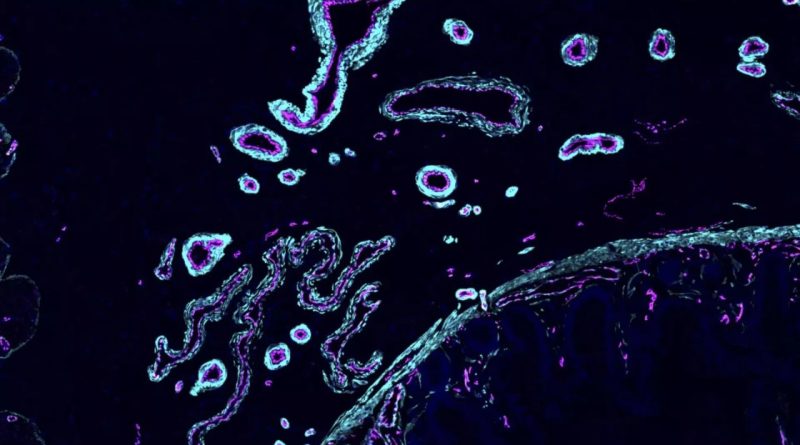

این محققان که در قالب پروژه کنسرسیوم بینالمللی «اطلس سلولهای انسانی» در بیشتر از ۱۰۰ سرزمین فعالیت میکنند، تلاش دارند شباهتها و تفاوتهای سلولهای افراد با پیشینههای جمعیتشناختی و ژنتیکی گوناگون را شناسایی کنند.

آنها این چنین بازدید کردند که هر سلول در کدام بافت گروهبندی میشود، در کجای بدن قرار دارد و چطور با گذشت زمان تحول میکند.

دانشمندان در کنسرسیوم بینالمللی اطلس سلولهای انسانی تا بحال ۱۰۰ میلیون سلول از بیشتر از ۱۰ هزار نفر در سراسر جهان را تحلیل کردهاند.

دانشمندان تصمیم دارند تا سال ۲۰۲۶ نسخهای کاملتری از اطلس سلولی را اراعه دهند که شناسههای سلولی را در ۱۸ اندام و سیستمهای بدنی گوناگون شامل پوست، قلب، سینهها و موارد دیگر پوشش میدهد.